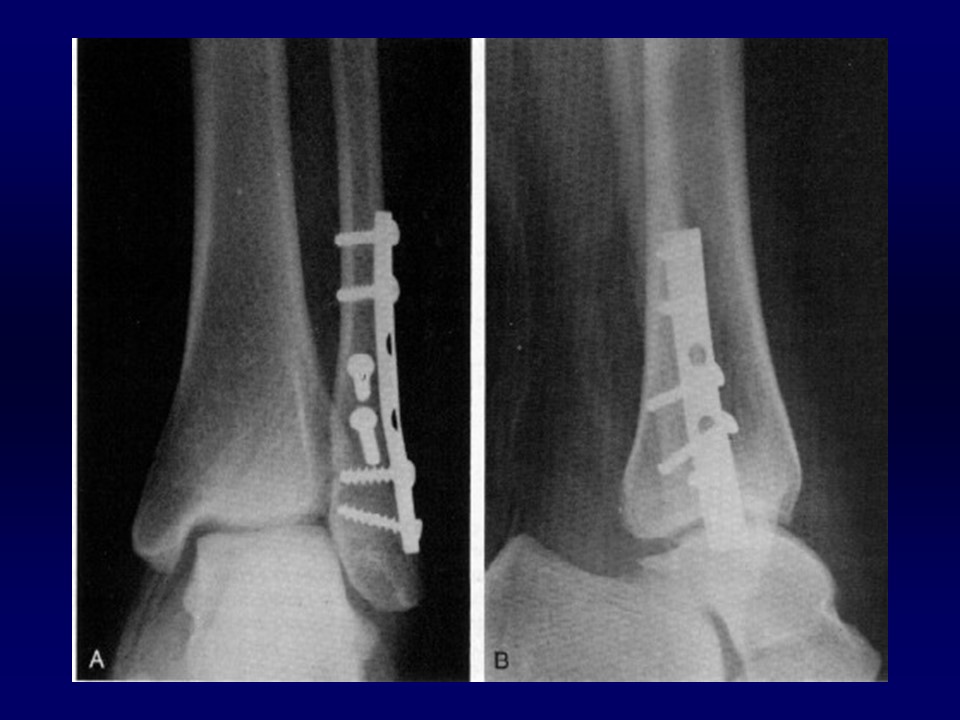

踝关节骨折的治疗PPT

Ramsey and Hamilton: 1 毫米的外移, 胫距关节接触面积将减少42%